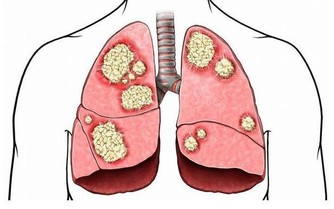

維生素A不但是保護靈魂之窗的重要元素,也能在呼吸道和腸胃自然形成一層保護膜,

防止細菌或有害物質的侵害。